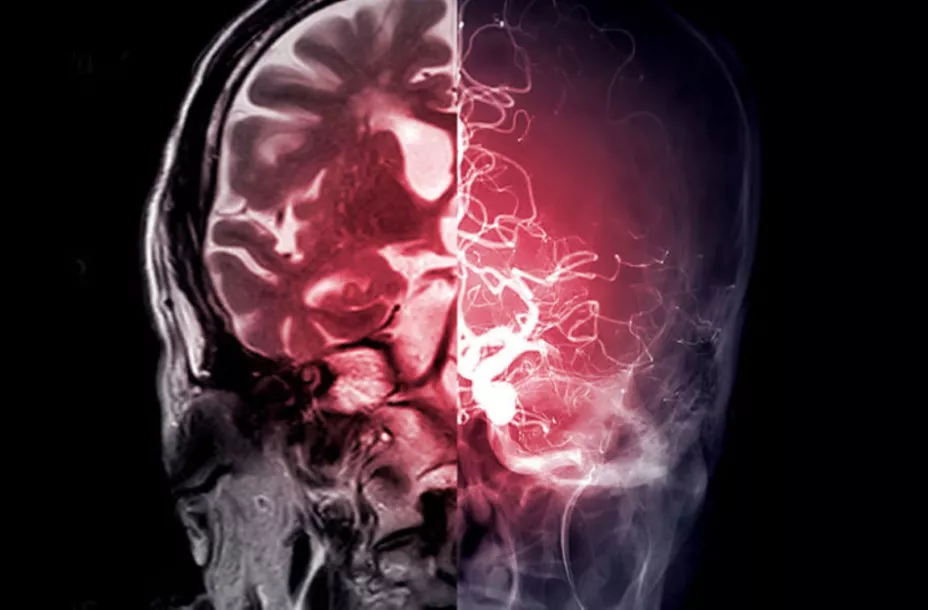

Cada participante se sometió a una intervención de ECP, que consistió en la implantación quirúrgica de electrodos en una parte del cerebro llamada cerebelo. Una vez conectados a un dispositivo similar a un marcapasos, los electrodos se utilizaron para administrar pequeños impulsos eléctricos que ayudaran a las personas a recuperar el control de sus movimientos.